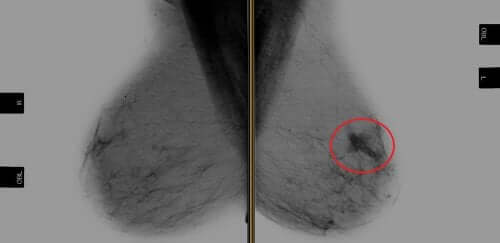

Trastuzumab è la prima terapia diretta contro un oncogene per pazienti con carcinoma mammario HER-2 positivo. Un oncogene è un gene che ha una grande capacità di mutazione o trasformazione che provoca la formazione di cancro in un tessuto.

D’altra parte, un cancro al seno di tipo HER-2 positivo si traduce in una neoplasia con recettori sovraespressi per questa proteina. Le proteine HER-2 sono recettori sulle cellule mammarie prodotte dal gene HER-2 e sono necessari. Queste proteine, di fatto, consentono alle cellule del seno di dividersi e ripararsi.

I tumori al seno HER-2 positivi rappresentano il 20-30% dei carcinomi mammari nell’essere umano. Questa neoplasia era correlata a una prognosi sfavorevole, inclusa una ridotta sopravvivenza priva di recidive e sopravvivenza globale.